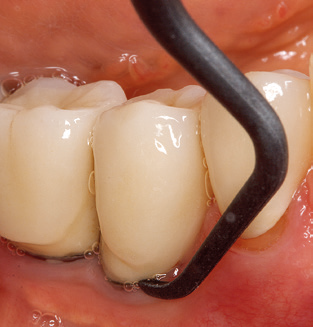

Nach der maschinellen Reinigung der Zahn­ und Implantatoberflächen erfolgt eine manuelle Instrumentierung der natürlichen Zahnoberflächen mit konventionellen Handinstrumenten. Bei der manuellen Reinigung ist insbesondere auf einen korrekten Anstellwinkel, eine ausreichende Schärfe, eine gute Abstützung und auf eine von apikal nach koronal gerichtete Arbeitsweise der Kürette zu achten. Zur Nachinstrumentierung der Implantatkonstruktionen sollten entweder Titan­ oder Carbonküretten verwendet werden (Abb. 8). Ergänzend zum Einsatz von Ultraschallgeräten können in der Erhaltungstherapie auch Pulverstrahlgeräte genutzt werden. Dabei ist jedoch zu berücksichtigen, dass diese Verfahren nicht zum Entfernen harter Beläge geeignet sind und daher die Verwendung von Hand­ oder Ultraschallinstrumenten nicht komplett ersetzen können. Abschließend erfolgt in jedem Fall eine mechanische Politur der zugänglichen Zahn­ und Implantatoberflächen mit Polierkelchen und Polierpasten (Abb. 9).

Abb. 4: Für das Sondieren an dentalen Implantaten sind biegsame, millimeterskalierte Sonden empfehlenswert (z.B. Colorvue Kit PCV11KIT6, Hu-Friedy). – Abb. 5a und b: Eine gerade Arbeitsspitze (1P, W&H Dentalwerk Bürmoos GmbH) ist universell für die Instrumentierung natürlicher Zähne geeignet. – Abb. 6: Für die Bearbeitung schwer zugänglicher Bereiche der Zahn- und Wurzeloberflächen (z.B. Furkationen) bieten sich gebogene Arbeitsspitzen (3Pr/3Pl, W&H Dentalwerk Bürmoos GmbH) an. – Abb. 7: Die spitz zulaufende sechseckige Implantatreinigungsspitze (1I, W&H Dentalwerk Bürmoos GmbH) ermöglicht eine atraumatische und effiziente Reinigung der Kronen- und Abutmentoberflächen. – Abb. 8: Für die manuelle Instrumentierung der Implantatoberflächen sind Titan- oder Carbonküretten geeignet.